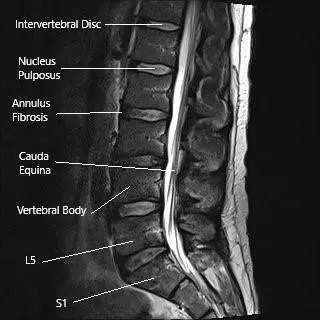

- MRI: The gold standard for detecting spinal cord and nerve compression, showing both soft tissue and bone detail.

MRI of lumbar spine in sagittal section

Spine tumors are abnormal growths within or around the spinal cord that can be benign or cancerous. Early diagnosis through MRI and biopsy is essential. Most patients benefit from surgical removal followed by radiation or chemotherapy, depending on the tumor type. Advances in microsurgery and imaging have made outcomes highly successful, improving pain relief, mobility, and overall quality of life.

What role does MRI play in diagnosing spine tumors?

MRI is crucial for evaluating soft tissue structures, bone marrow involvement, and the relationship of the tumor to the spinal cord and nerves. It provides detailed information that helps in planning treatment.